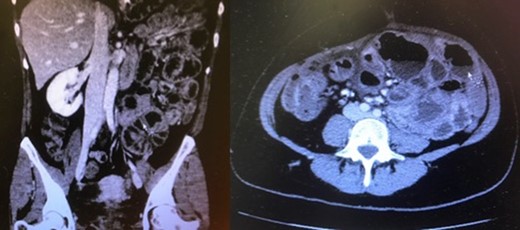

The patient was lastly readmitted for abdominal distension, vomiting and obstipation. Bowel obstruction was suspected. A computed tomography (CT) of the abdomen and pelvis with intravenous contrast injection was performed. It showed dilated small-bowel in the left flank with non-distended distal bowel loops (Fig. 1), consistent with an asymmetrical abdomen that was more distended on the left side. No obvious transition point could be objectified. The clinical presentation and imaging were suggestive of SBO. After several days of unsuccessful conservative management with a nasogastric tube and intravenous hydration, she was taken to the operating room where an exploratory laparotomy revealed a hick adherent fibrous sheath that was encapsulating most of the small bowel (Fig. 2). Extensive adhesiolysis and laborious excision of the capsule were performed and ‘Seprafilm’, an adhesion barrier, was applied [2]. A severely stenotic 10 cm bowel segment was resected and reanastomosed. The postoperative period was complicated with pulmonary embolism, ileus and ascites. Nonetheless, she recovered well and was eventually discharged.

Distended small-bowel loops located mainly in the left hemiabdomen.

CT of the abdomen and pelvis can be helpful in identifying SEP. A finding such as a clustered array of dilated bowel loops, referred to sometimes as the ‘Cauliflower sign’ can be objectified. Abdominal imaging consists otherwise of unspecific findings of bowel dilation and unique or multiple transition areas in keeping with an obstructive process [8, 9].